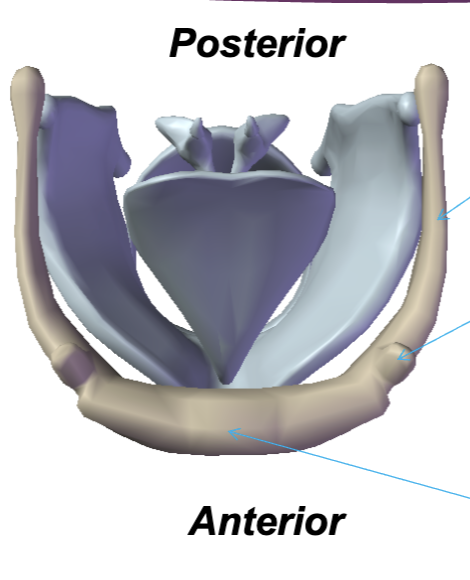

Hyoid bone

Where are the parts of the hyoid bone from top to bottom?

Greater cornu, Lesser cornu, Corpus

Thyroid cartilage

Cricoid Cartilage

Epiglottis

Arytenoid cartilages